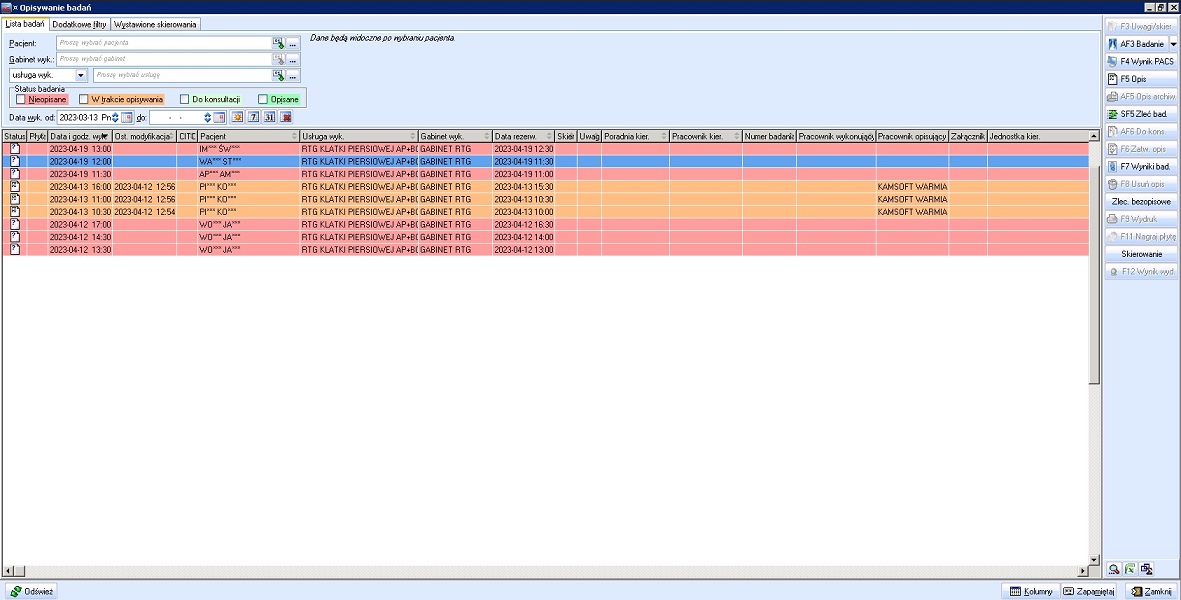

Rozwiązanie zawiera wszystkie elementy informatyczne umożliwiające obieg informacji medycznej, pozwala na tworzenie i udostępnianie elektronicznej dokumentacji medycznej EDM. Integracja pomiędzy systemem medycznym i systemem PACS umożliwia przekazywanie zleceń na badania i odbieranie wyników oraz rozliczenia usług. Opcjonalnie system umożliwia wysyłanie badań do zdalnego opisu.

- Oprogramowanie pracowni diagnostyki obrazowej (RIS)

- Serwer przechowujący wyniki badań (PACS)

- Przeglądarka diagnostyczna DICOM do opisu badań